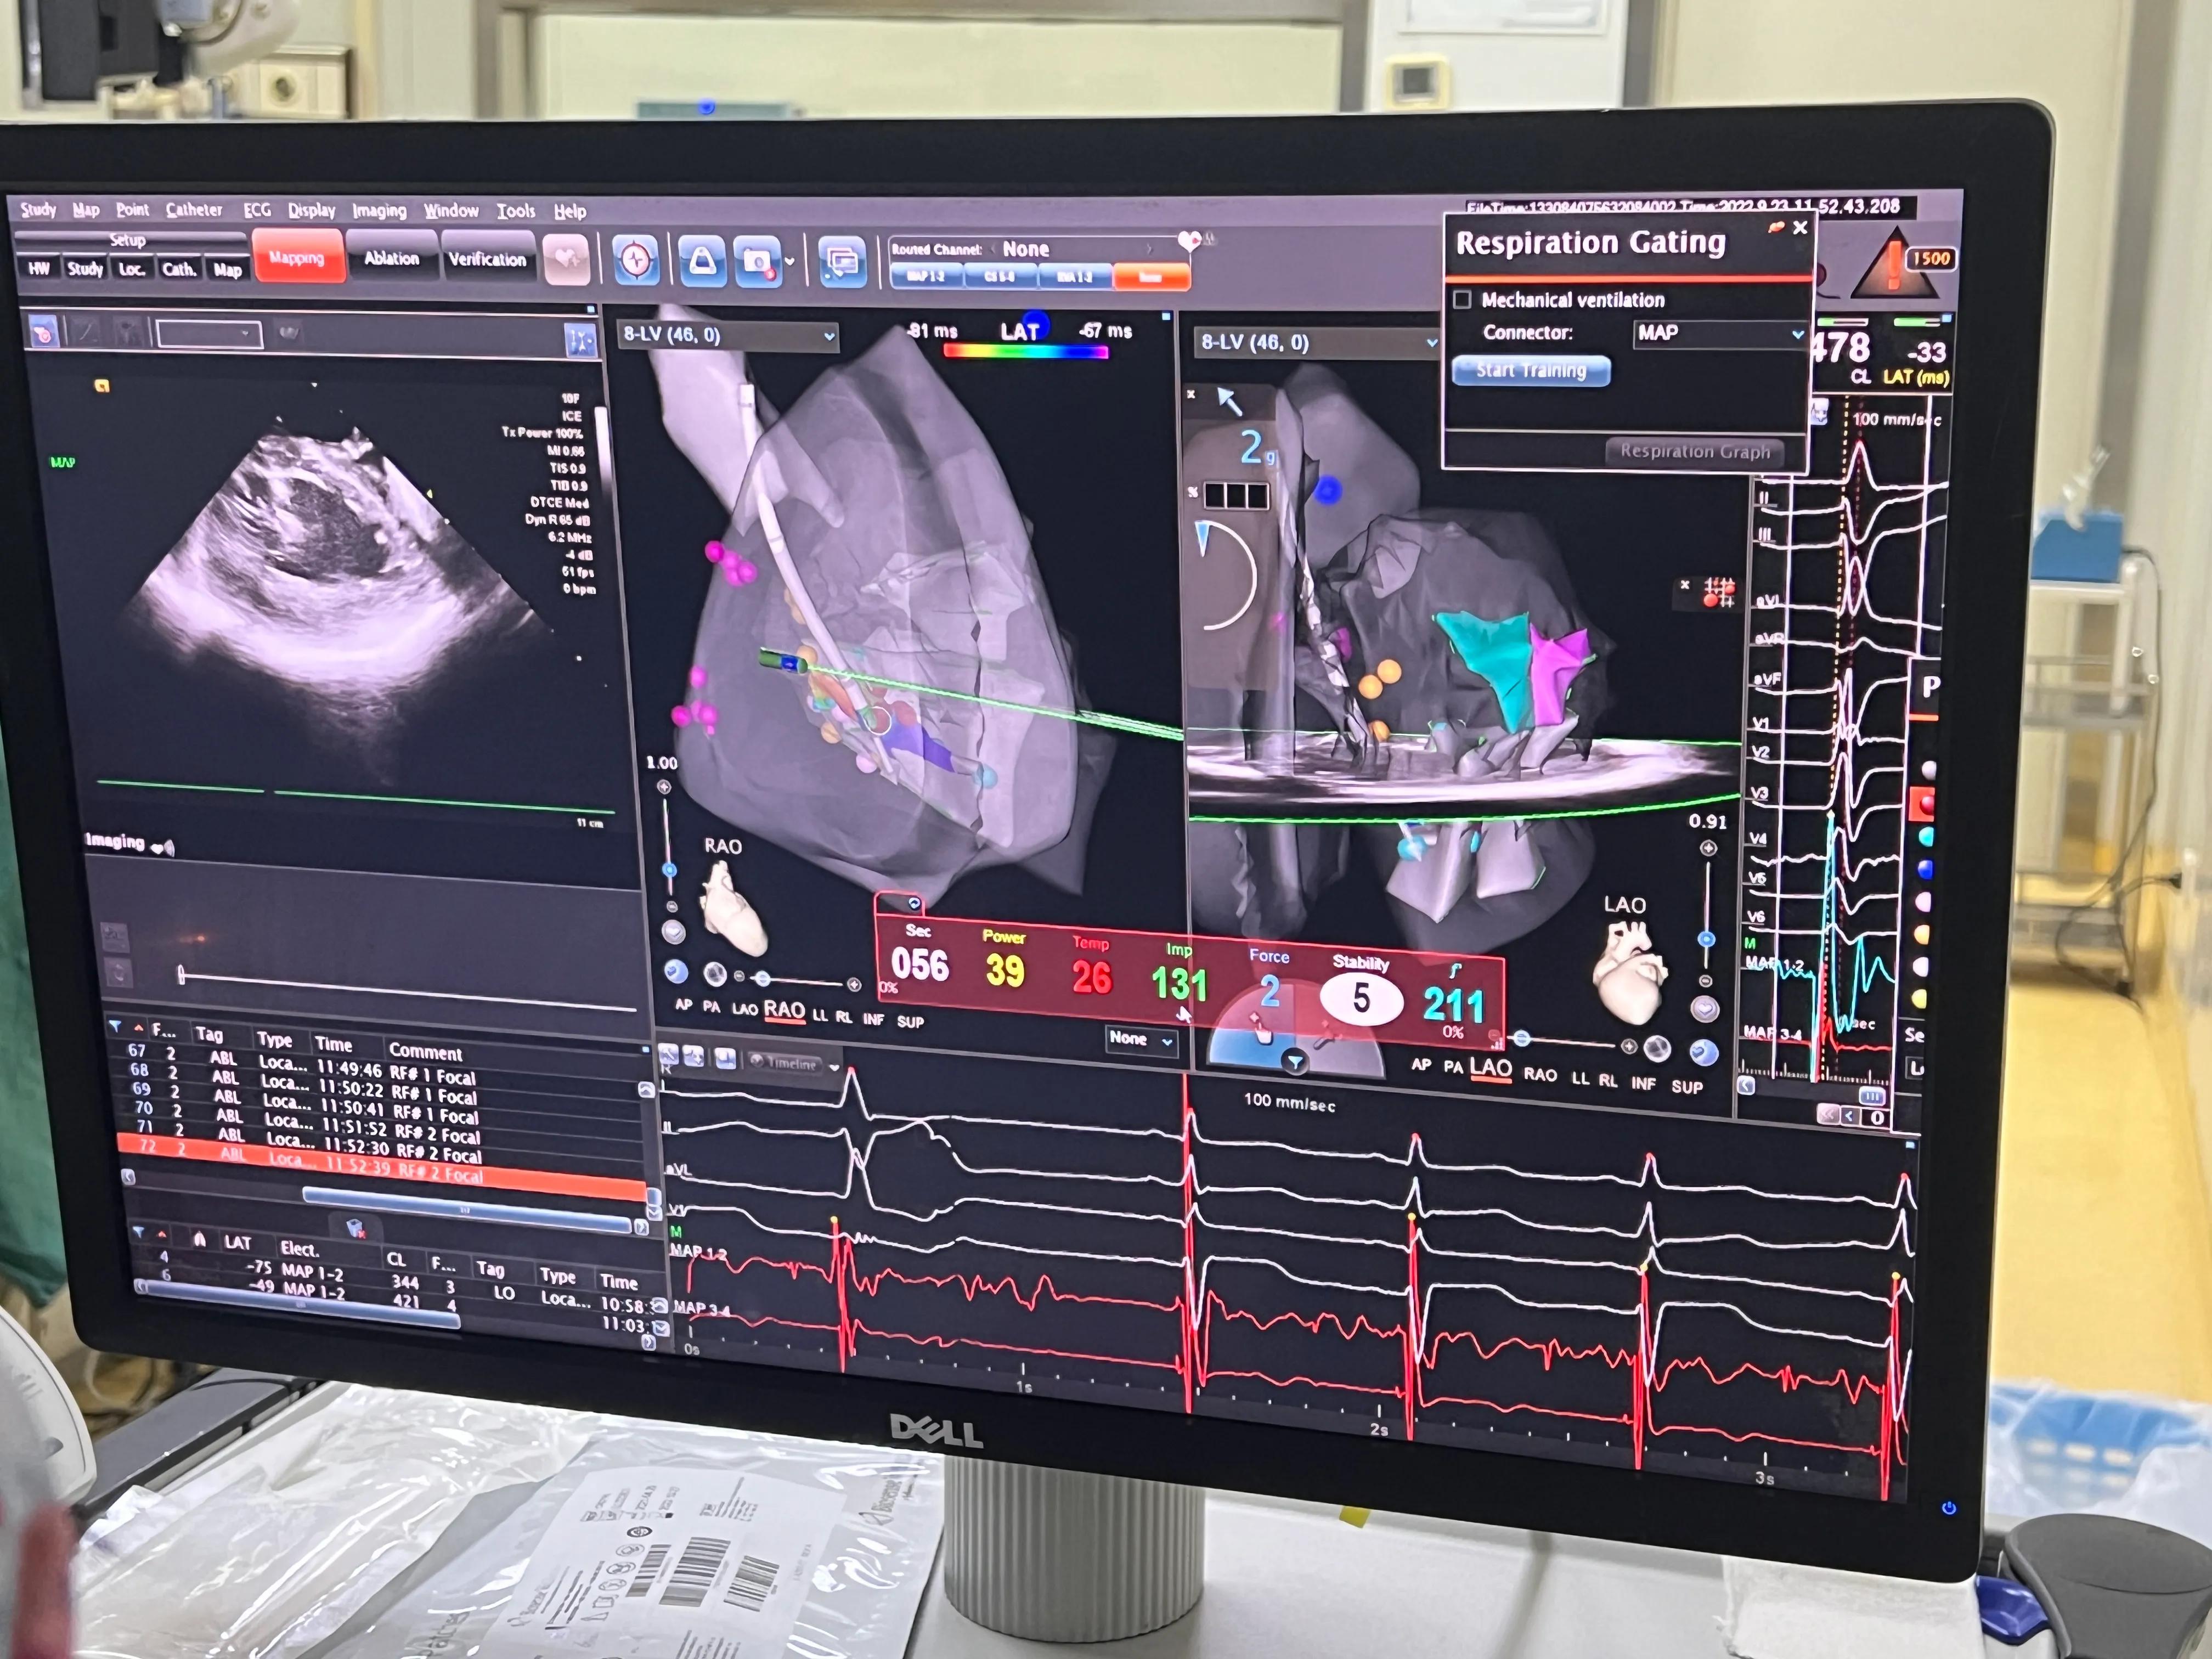

图5:术前我们需要取baseline线,术中消融大头到位后与baseline比较早搏形态是否一致。另外,我们可以看到,V1导联呈M型,胸导联QRS波较宽

大头到位后,时时动态分析相似性

大头到位后起搏大头,比较相似性,寻找准确早搏起源位置,在大头到达左后乳头肌间隔侧,相似性达98%,领先体表29ms,锁定病灶。

消融功率40W,盐水走速15ml/min